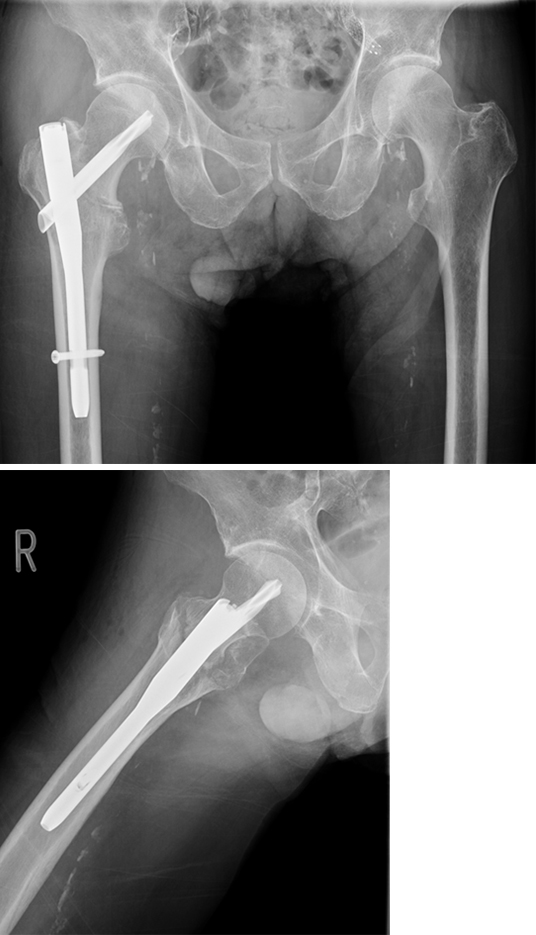

An 83-year-old female patient sustained a 31-A.2.2 fracture of the right proximal femur after a fall at home (Figs 1-2). Intraoperative and postoperative images are shown (Figs 3-5).

Case provided by Michael Blauth, Innsbruck, Austria